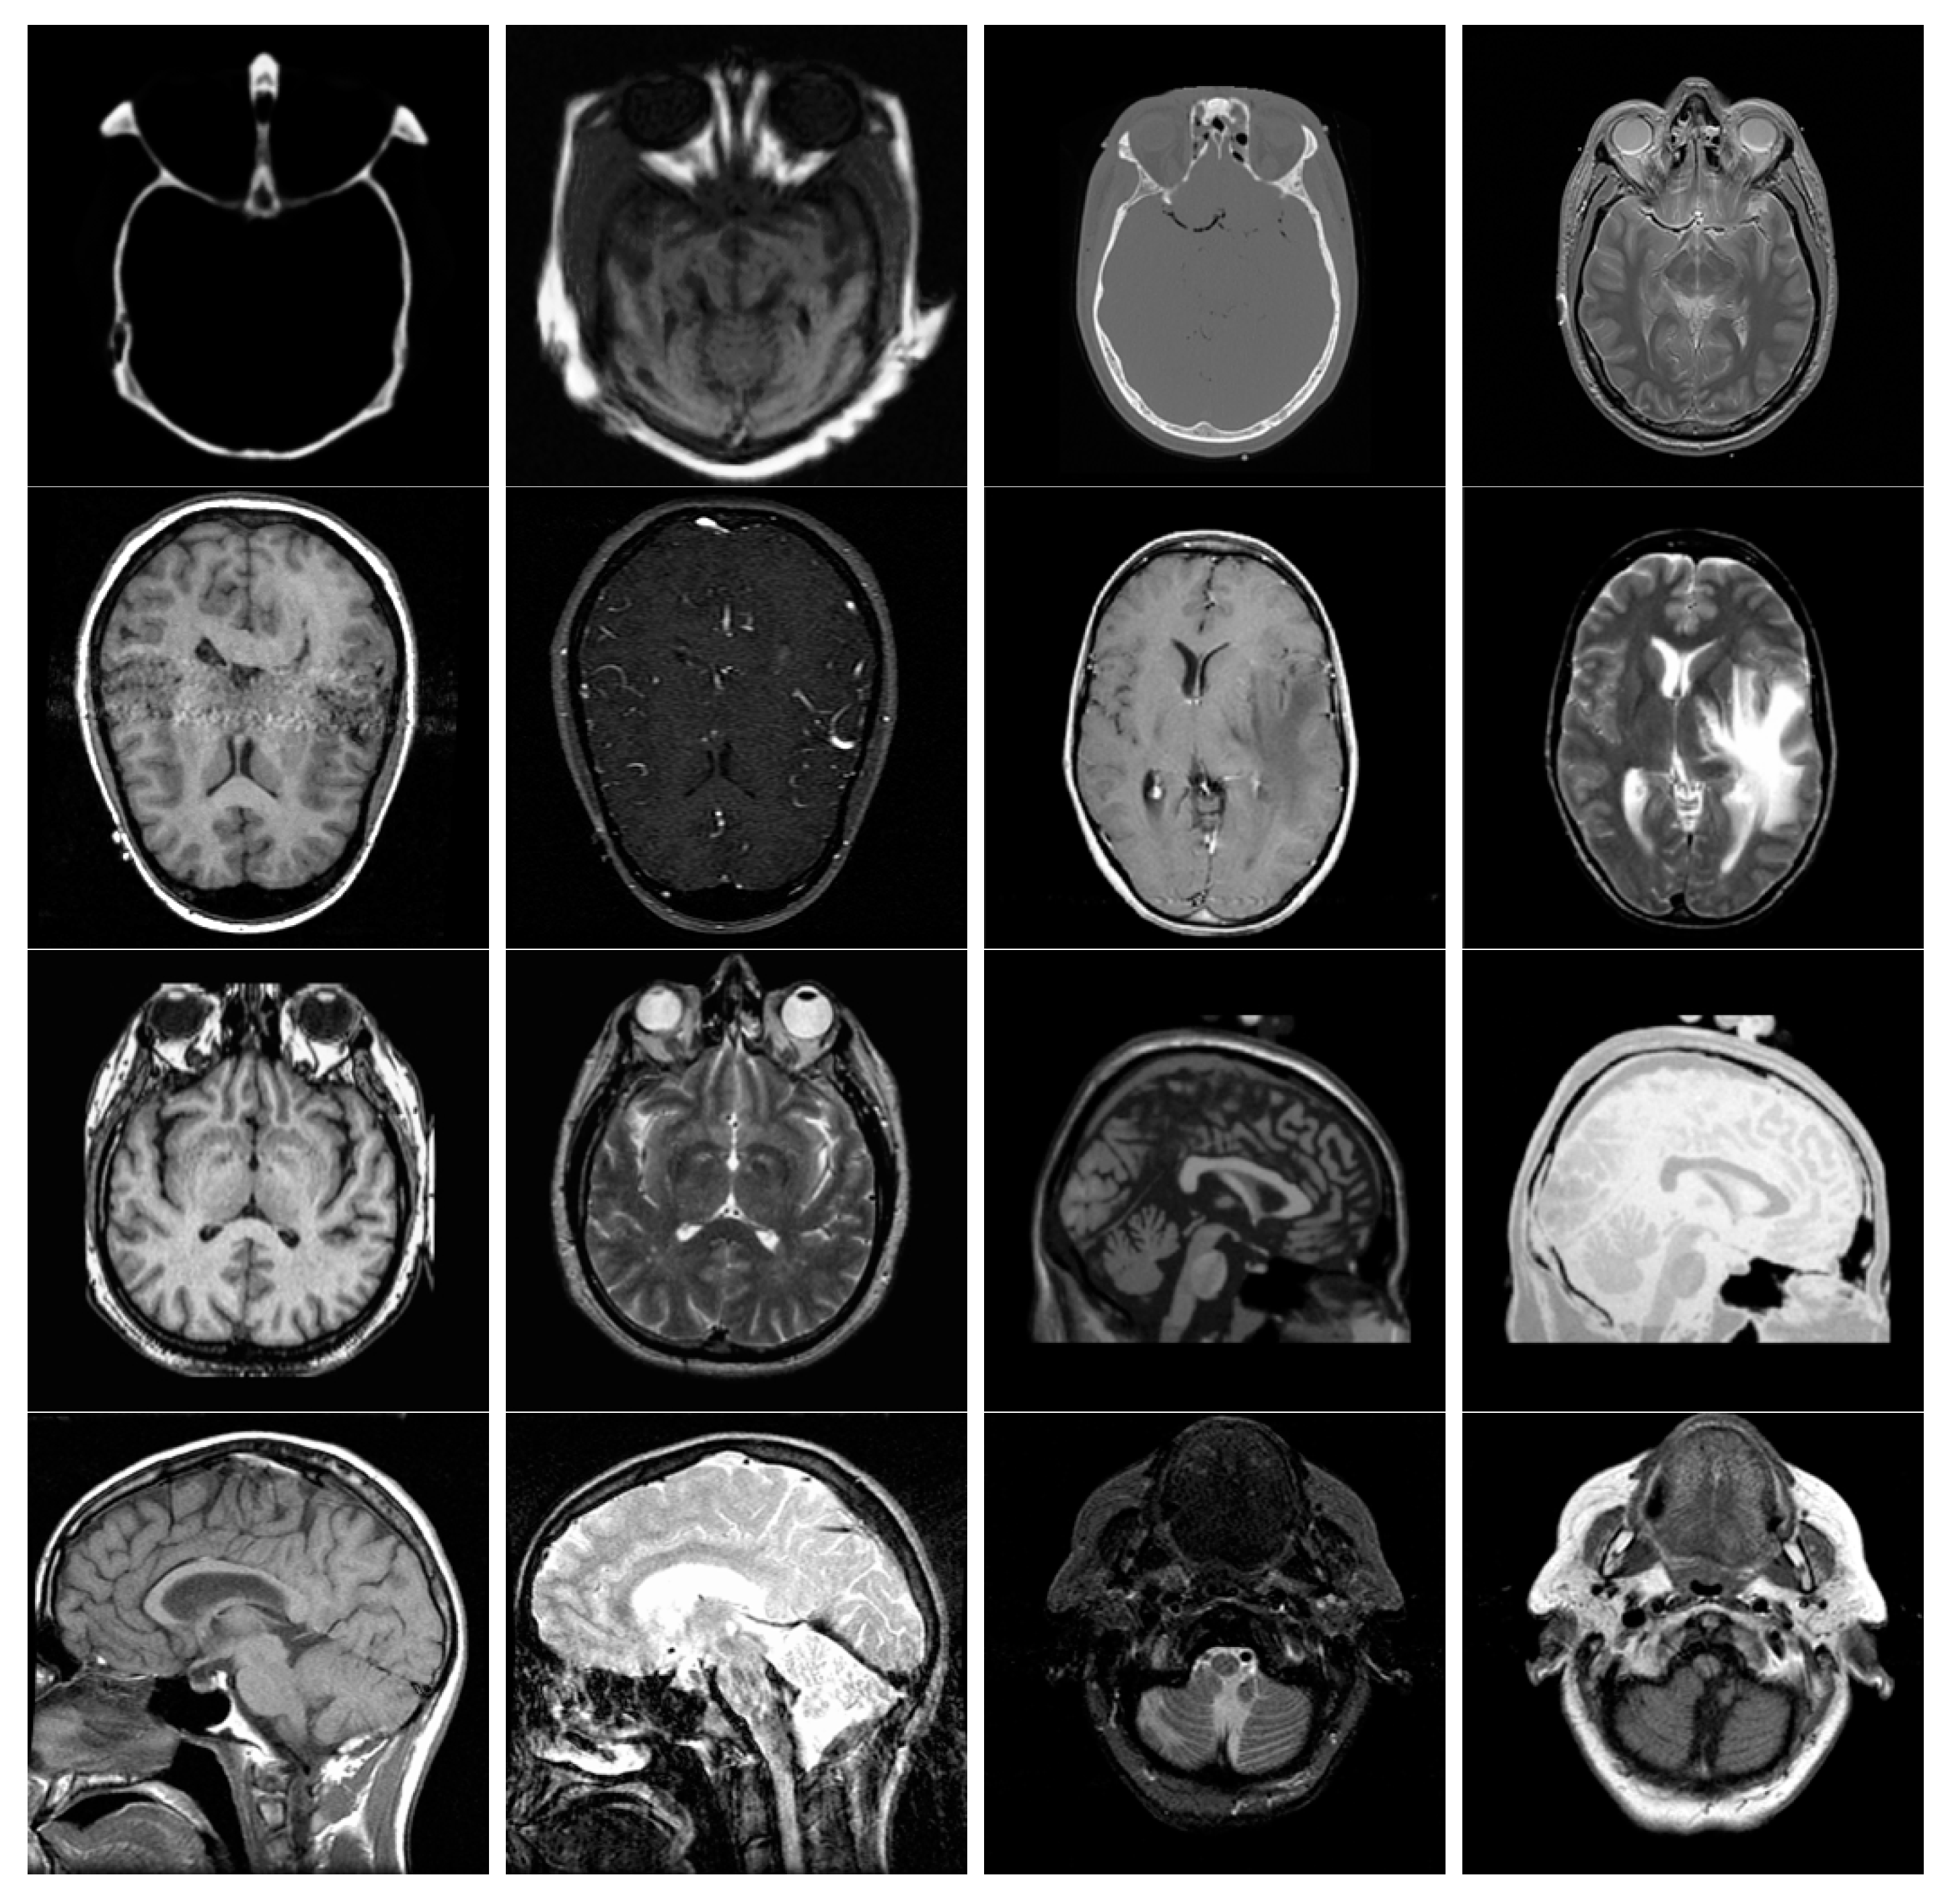

The multi-modal medical image dataset had eight pairs of images, which are shown in Figure 9. The multi-sensor infrared and visible image dataset had 14 pairs of images, which are shown in Figure 10. The multi-focus dataset had 20 pairs of images, which are shown in Figure 11. And the multi-exposure image dataset had six pairs of images, which are shown in Figure 12.

Figure 9. Multi-modal medical images used in the experiments.

Entropy 25 01215 g009